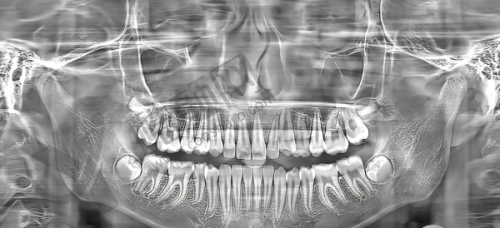

设备方面,门诊部引进了一系列精良的牙科设备。数字化X线系统能提供高清晰度的影像,帮助医生全方面分析牙齿情况;激光治疗设备可实现无创、微痛的治疗成效,减少患者的痛苦,确保治疗的精细性和效率高性。